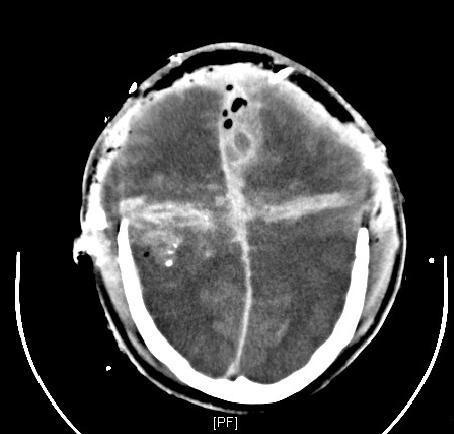

Craniocerebral gunshot injuries are often lethal, especially after suicide attempts. The treatment of non space consuming haematomas and the indications for invasive pressure measurement are controversial. Civilian gunshot injuries to the torso mostly intend to kill; however for those patients who do not die at the scene and are hemodynamically stable, insertion of a chest tube is usually the only required procedure for the majority of penetrating chest injuries. In penetrating abdominal injuries there is a trend towards non-operative care, provided that the patient is hemodynamically stable. Spinal gunshots can also often be treated without operation. Gunshot injuries of the extremities are rarely life-threatening but can be associated with severe morbidity.With the exception of craniocerebral, bowel, articular, or severe soft tissue injury, the use of antibiotics is controversial and may depend on the surgeon's preference.

颅脑枪伤通常是致命的,尤其是在自杀未遂后。对于非占位性血肿的治疗以及有创压力测量的指征存在争议。平民躯干枪伤大多意图致死;然而,对于那些没有在现场死亡且血流动力学稳定的患者,对于大多数穿透性胸部损伤而言,插入胸管通常是唯一所需的操作。对于穿透性腹部损伤,如果患者血流动力学稳定,则有采用非手术治疗的趋势。脊柱枪伤通常也可以不通过手术进行治疗。四肢枪伤很少危及生命,但可能伴有严重的发病率。除了颅脑、肠道、关节或严重软组织损伤外,抗生素的使用存在争议,可能取决于外科医生的偏好。